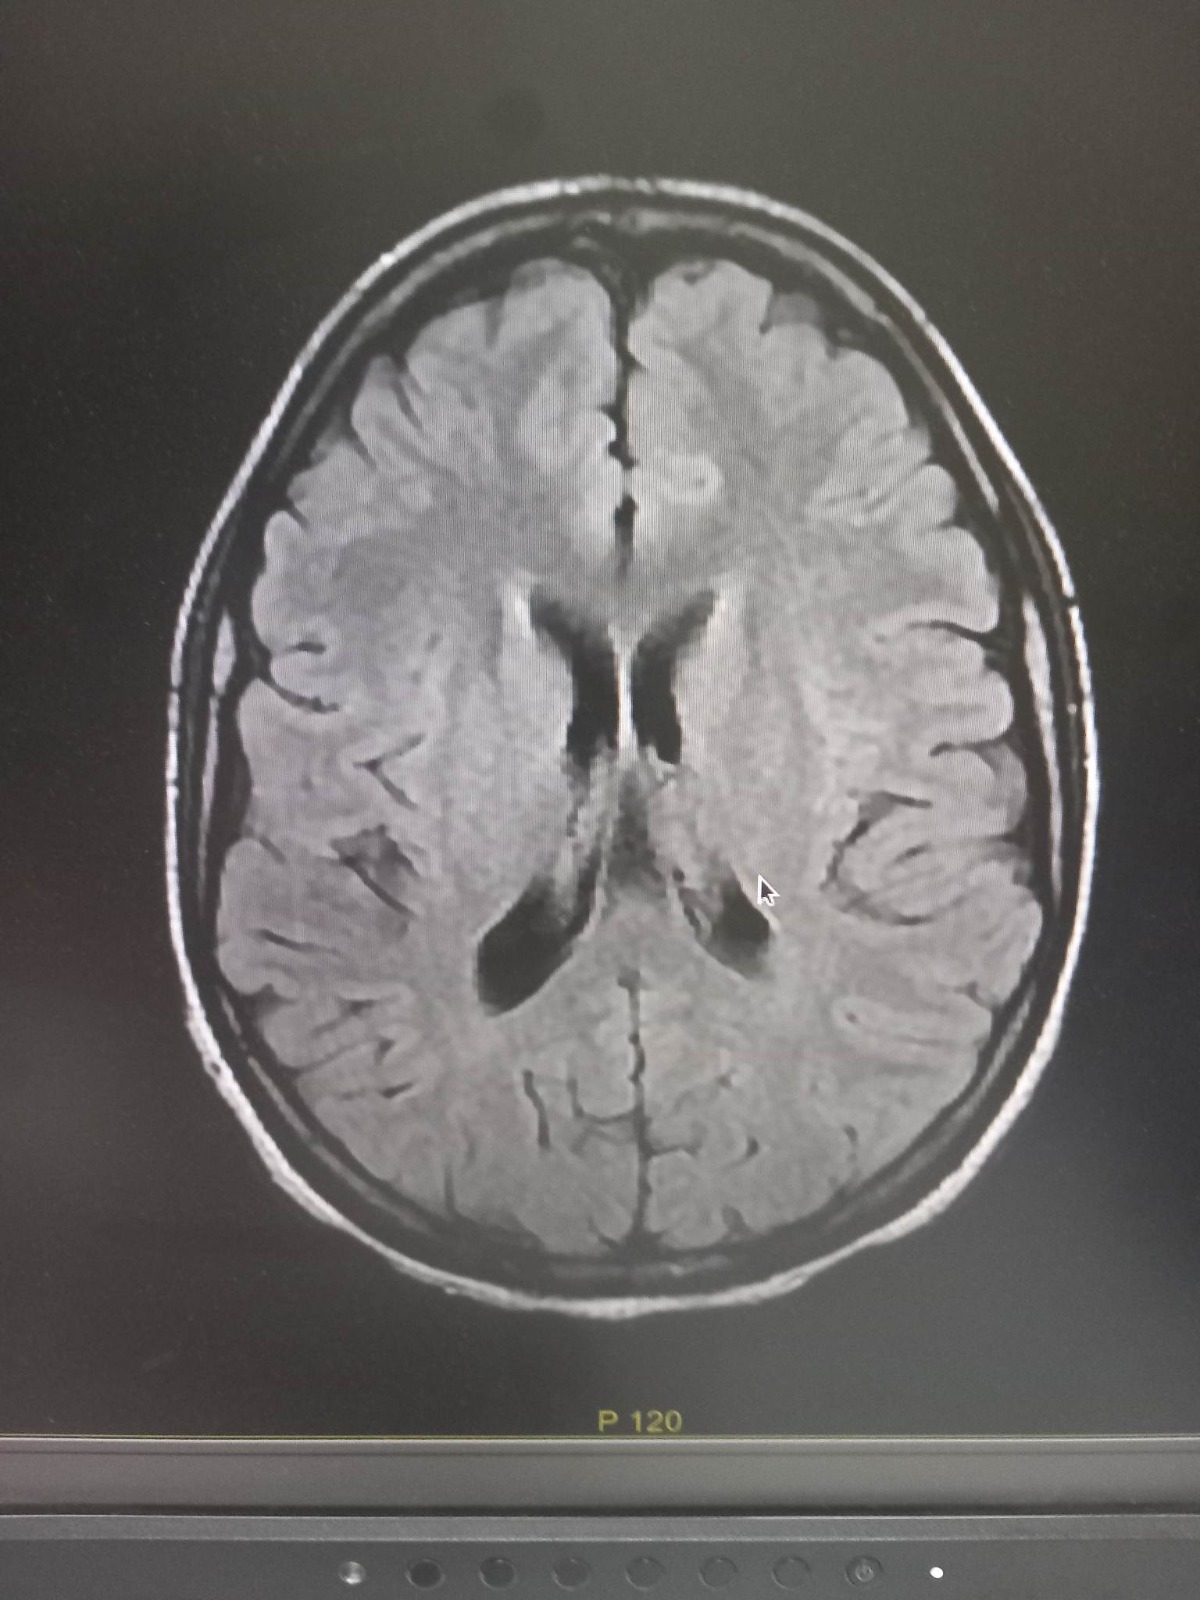

جاء ذلك بعد صدور نتائج التشريح الطبي الذي أجري في مختبر بالخارج، وأكد أن وفاة جوب كانت نتيجة سكتة قلبية على إثر تناول جرعة كبيرة من الكوكايين.